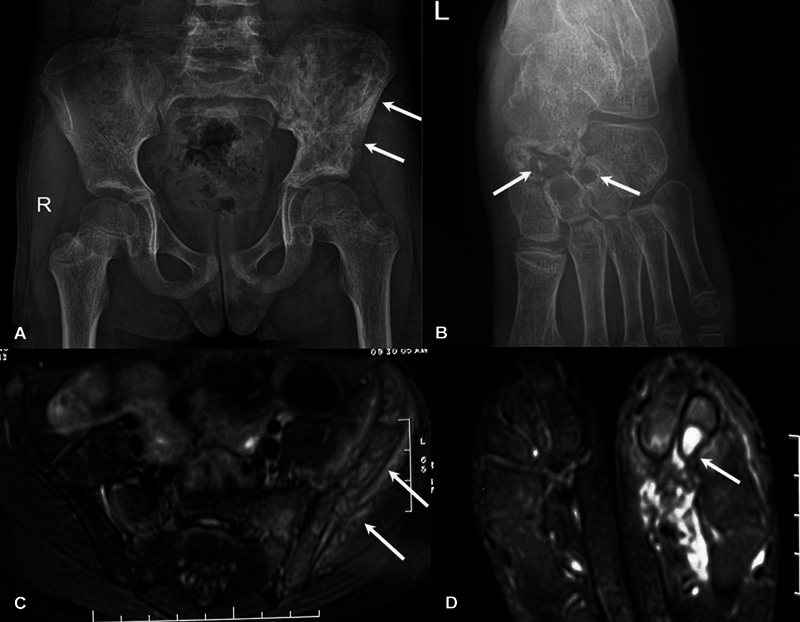

慢性非感染性骨髓炎或慢性非细菌性骨髓炎(CNO),也称为慢性复发性多灶性骨髓炎,是一种主要影响儿童年龄组的自身炎症性骨疾病。目前,该病的诊断主要基于临床、实验室和影像学特征。影像学在CNO的诊断和随访中起着至关重要的作用,全身磁共振成像(WBMRI)是主要方式。x光片有助于排除常见的鉴别诊断,如感染和恶性肿瘤。WBMRI有助于疾病检测和鉴别诊断的排除,识别额外的病变,并在确定骨骼受累模式方面发挥作用,有助于预测和分级。最近对WBMRI上特定形态和分布模式的认识越来越多地允许仅通过成像对该实体进行预先诊断。这也有助于在随访中评估对治疗的反应。本文旨在总结影像学在CNO评估中的作用,特别强调WBMRI在其评估中的作用。

Chronic noninfectious osteomyelitis or chronic nonbacterial osteomyelitis (CNO), also known as chronic recurrent multifocal osteomyelitis, is an autoinflammatory bone disorder primarily affecting the pediatric age group. Currently, it is diagnosed on the basis of clinical, laboratory, and imaging features. Imaging plays a crucial role in the diagnosis and follow-up of CNO with whole body magnetic resonance imaging (WBMRI) being the main modality. Radiographs assist in exclusion of common differential diagnoses like infections and malignancy. WBMRI aids in disease detection and exclusion of differential diagnoses, identifies additional lesions, and has a role in ascertaining the pattern of bony involvement which helps with prognostication and grading. Recent recognition of specific morphological and distribution patterns on WBMRI is increasingly allowing an upfront diagnosis of this entity to be made on imaging alone. It is also helpful for assessment of response to therapy during follow-up. This review aims to summarize the role of imaging in the evaluation of CNO, with special emphasis on WBMRI in its assessment.